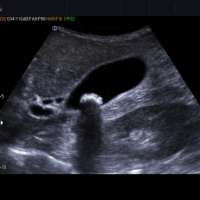

Hamiləlik dövründə ultrasəs müayinənin qiymətləndirilməsi

Ultrasəs hazırda hamiləlik müayinələrinin ən mühüm hesab olunanıdır. Hamiləlikdə heç bir problem olmasa da müəyyən vaxtlarda müəyyən fasilələrlə ultra səs nəzarəti aparılır. Hamiləliyin fərqli aylarında ultrasəslə fərqli dəyərləndirmələr aparılır. Məsələn, hamiləliyin ilk aylarında yalnız körpənin kilosu ölçülməz ürək adımı və uşaqlığın böyüklüyü kimi qiymətləndirmələr aparılır, hamiləliyin 5-ci ayında kilosu, suyu, plasentanın vəziyyəti, orqanların strukturu kimi daha ətraflı qiymətləndirmə aparılır, bunlardan başqa da fərqli aylarda fərqli dəyərləndirmələr aparılır.

Ultrasəs qiymətləndirməsi ilə təxminən 30-35 faiz uşaqda anomaliya olsa belə bilinməyə bilir. Yəni ultrasəs körpədəki inkişafla bağlı pozuntuların çoxunu müəyyən etsə də hər zaman hamısını müəyyən etməsi imkansızdır.

Ultrasəs müayinə (sonoqrafiya) – insan bədəninin, demək olar ki, bütün orqanlarının müayinəsi üçün istifadə olunan qeyri-invaziv instrumental müayinə metodudur. Metodun təməlini, insan orqanizminin toxumalarından keçib, həmin toxumaların sıxlığından asılı olaraq fərqli şəkildə əks olunan, ultrasəs dalğalarının ötürülməsi təşkil edir.